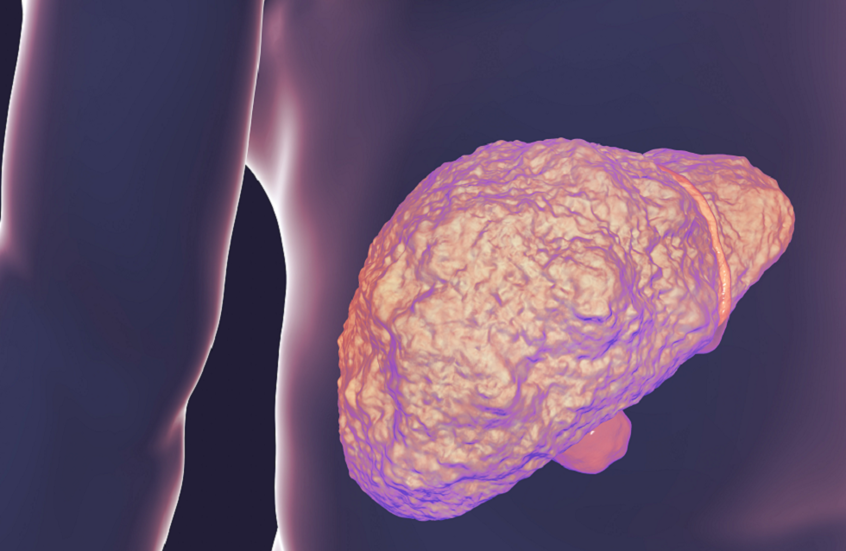

دور الكوليسترول في تدهور صحة الكبد

أظهر باحثون أن بلورات الكوليسترول في الكبد قد تؤدي إلى تصلبه في مرحلة مبكرة لدى المصابين بمرض الكبد الدهني المرتبط باضطراب التمثيل الغذائي (MASLD)، قبل ظهور التندب بفترة طويلة.

وقد تساعد هذه النتائج على تفسير تفاقم هذا النوع من أمراض الكبد نتيجة ارتفاع الكوليسترول، وتفتح فرصا جديدة للتشخيص والعلاج المبكرين.

وقالت الدكتورة ريبيكا جي. ويلز، أستاذة أمراض الجهاز الهضمي والكبد والمعدّة الرئيسية للدراسة: "لطالما شكّل التنبؤ بصحة الكبد، خصوصا لدى المصابين بمرض الكبد الدهني المرتبط باضطراب التمثيل الغذائي، تحديا كبيرا للأطباء، إذ إن حوالي ثلث سكان العالم لديهم تراكم دهون في الكبد، لكن نسبة قليلة منهم تصاب بأمراض كبدية خطيرة".

وأضافت أن الكشف عن بلورات الكوليسترول وتطوير طريقة سهلة للكشف عنها قد يساعد الأطباء على تحديد المرضى الأكثر عرضة لخطر الإصابة بأمراض كبدية حادة، ما يتيح التدخل المبكر عبر تشجيع العادات الغذائية الصحية أو مراقبة المرضى وتقديم العلاج قبل حدوث أضرار جسيمة.

تراكم الدهون في الكبد وخطورته

يحدث MASLD عندما تتراكم الدهون الزائدة في الكبد. وفي بعض الحالات، قد يحتاج المرضى إلى زراعة كبد أو يصابون بسرطان الكبد. ويرتبط تراكم الدهون بالسمنة ومقاومة الأنسولين وداء السكري من النوع الثاني، وغالبا ما يترافق مع سوء التغذية، بينما يلعب الاستعداد الوراثي دورا لدى بعض الأفراد.

وفي المختبر، أعطى فريق البحث من كلية بيرلمان للطب بجامعة بنسلفانيا، الفئران نظاما غذائيا غنيا بالدهون والكوليسترول أو نظاما غنيا بالدهون فقط. وأدى كلا النظامين إلى تشحم الكبد، أي تراكم الدهون في خلايا الكبد. لكن الفئران التي تناولت نظاما غنيا بالدهون والكوليسترول طورت بلورات في أكبادها، وكانت أكبادها أكثر صلابة مقارنة بالفئران الأخرى. ومن الجدير بالذكر أن قياس البلورات كان ممكنا فقط عبر الخزعة الجراحية.

بلورات الكوليسترول وعلاجات محتملة

أظهرت الدراسة أن بلورات الكوليسترول تصلّب أنسجة الكبد وتخلق بيئة تهيئ لمزيد من التندب. وقد تمكن الباحثون من عكس تصلب الكبد عبر إزالة البلورات في الفئران، رغم أن الطريقة لم تُطبق على البشر بعد.

وتظل هناك تحديات أمام التطبيق السريري، إذ لا يمكن قياس البلورات إلا بالخزعة، ما يحتم تطوير طريقة دقيقة وغير جراحية لتحديد المرضى الأكثر عرضة لخطر تلف الكبد.

وعلى الرغم من أن الستاتينات معروفة بقدرتها على خفض الكوليسترول في الدم، يأمل الباحثون في أن تساعد هذه الأدوية أو تدخلات أخرى متاحة على معالجة بلورات الكوليسترول في الكبد في المستقبل.

نشرت الدراسة في وقائع الأكاديمية الوطنية للعلوم.

المصدر: ميديكال إكسبريس